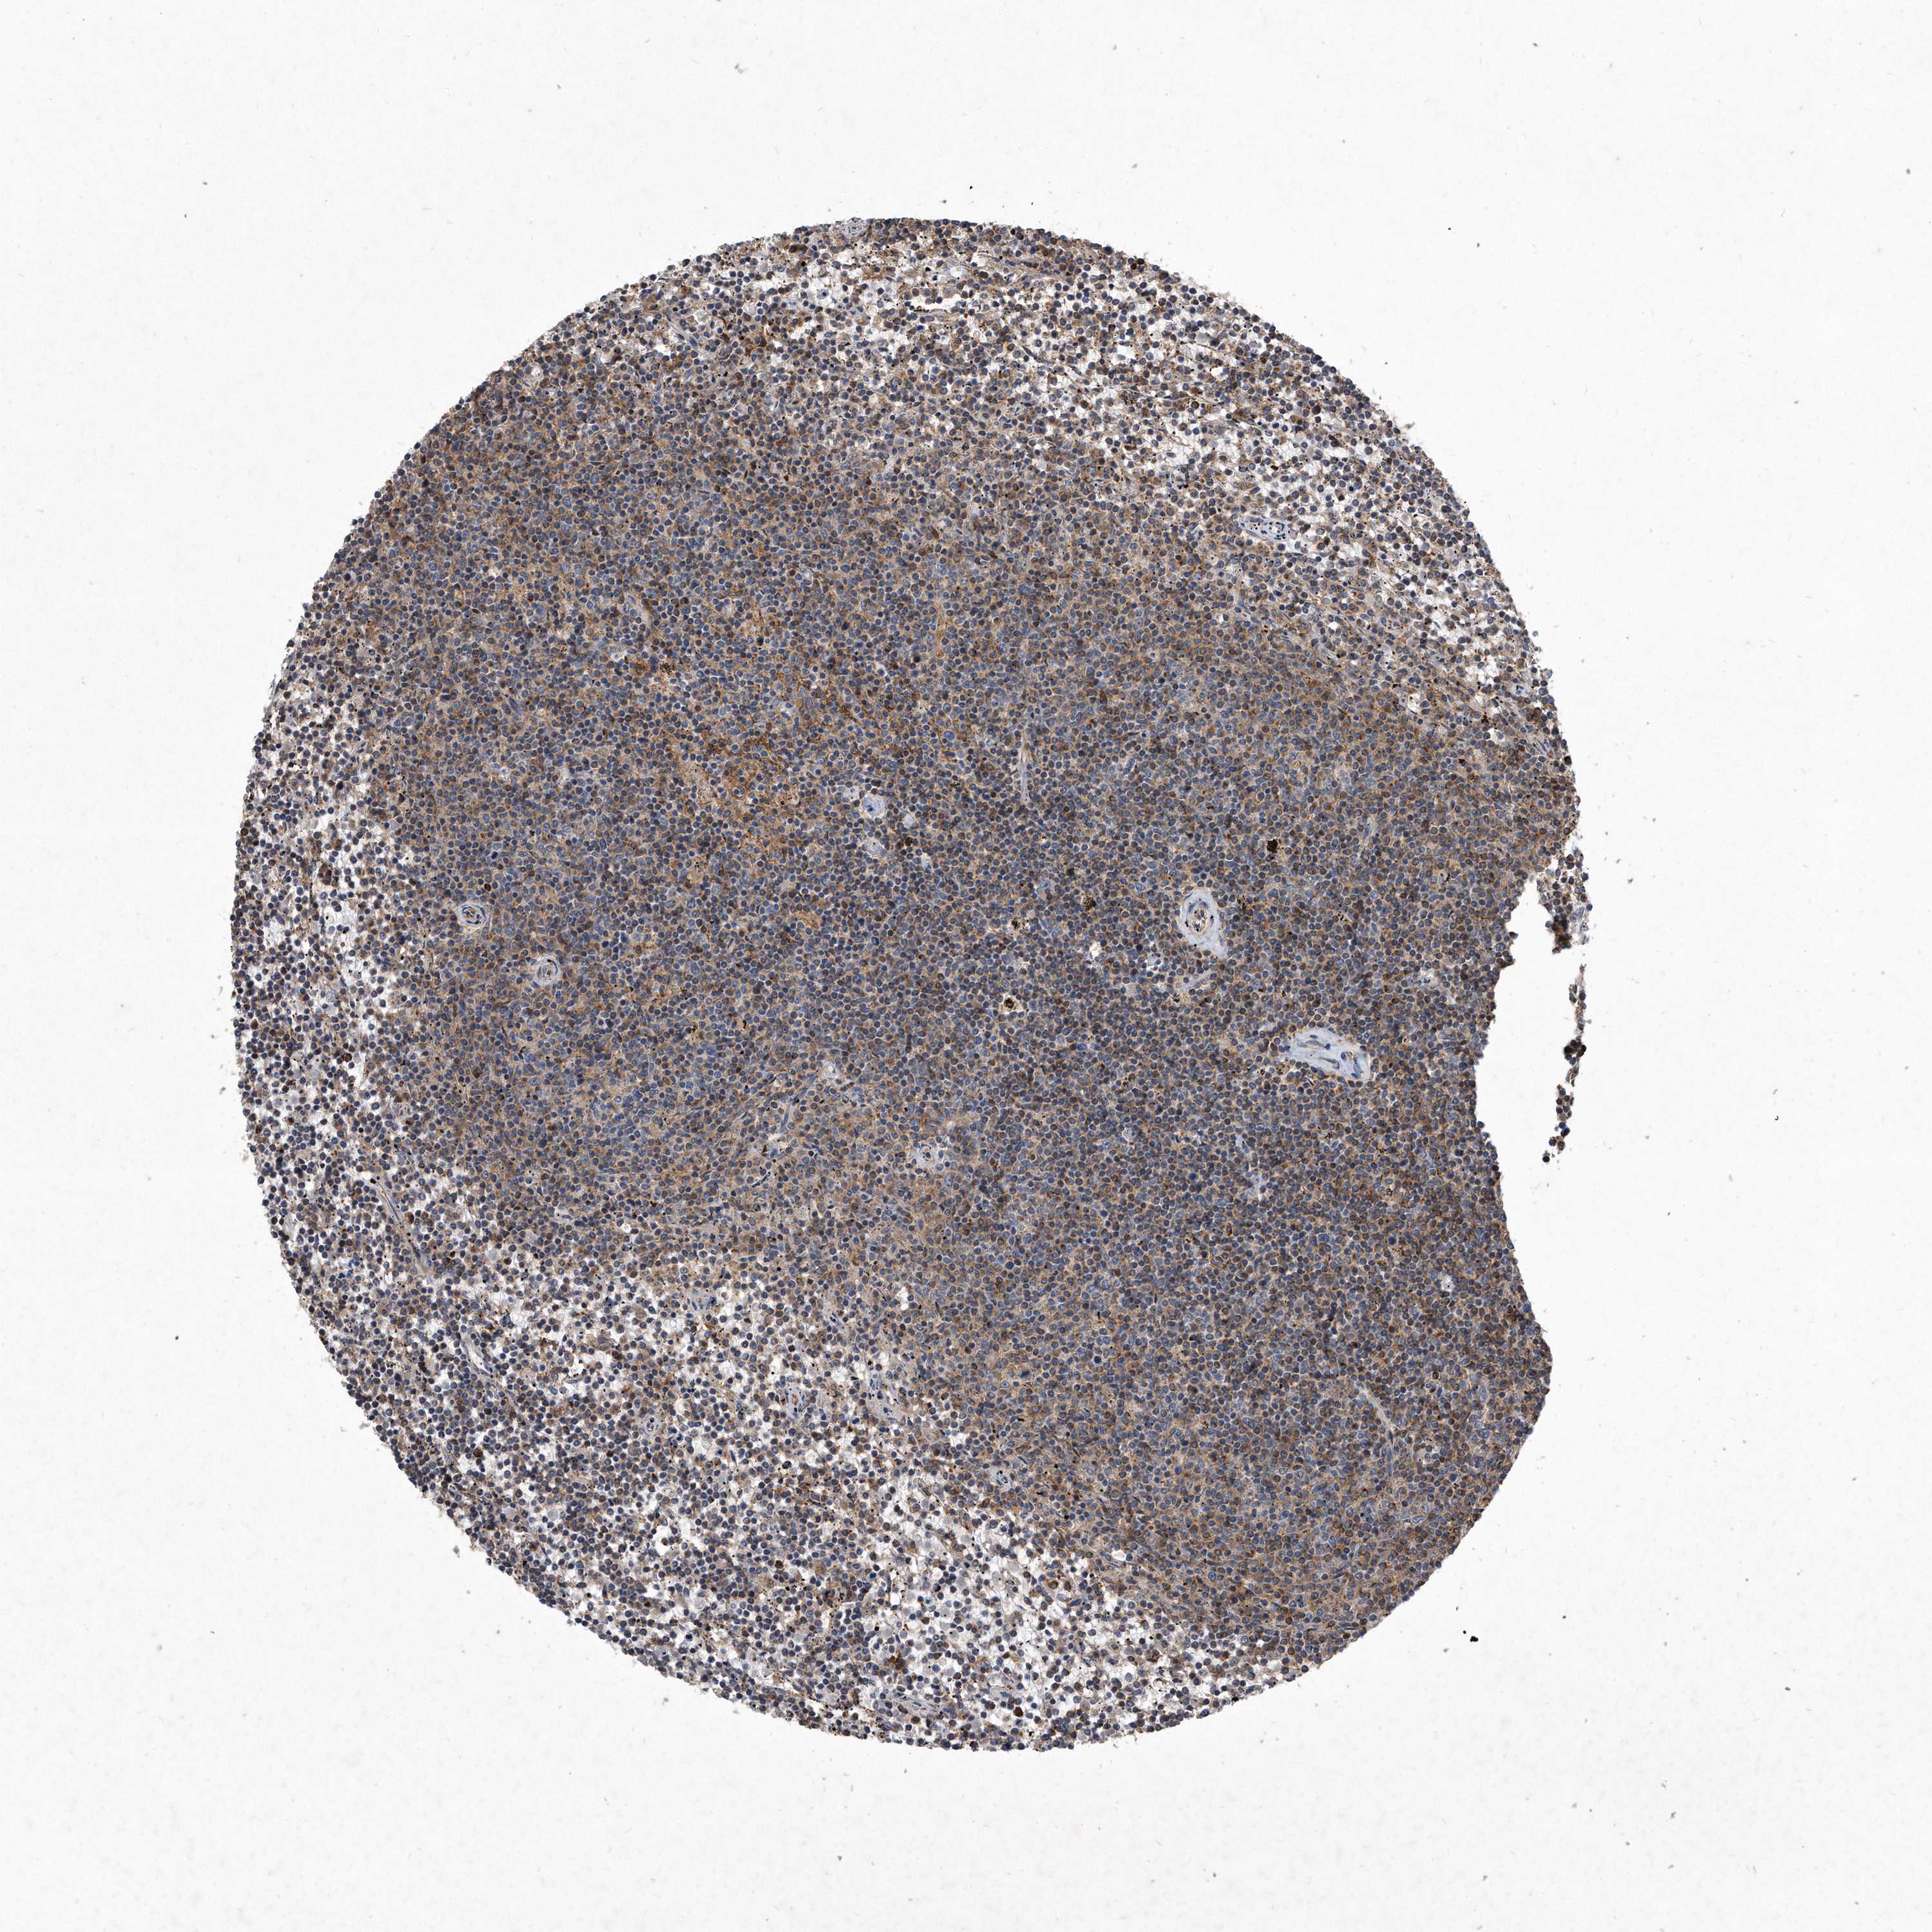

CANCER LYMPHOMA Show tissue menu

LYMPHOMA - Protein expressioni

A mouse-over function shows sample information and annotation data. Click on an image to view it in a full screen mode. Samples can be filtered based on level of antibody staining by selecting one or several of the following categories: high, medium, low and not detected. The assay and annotation is described here.

Each image is clickable and will lead to virtual microscopy that enables deeper exploration of all samples and also displays staining intensity scores, fraction scores and subcellular localization as well as patient and tissue information for each sample.

Antibody HPA029888

Antibody HPA029889

Antibody HPA029890

Hodgkin's disease, NOS

Malignant lymphoma, non-Hodgkin's type, High grade

Malignant lymphoma, non-Hodgkin's type, Low grade